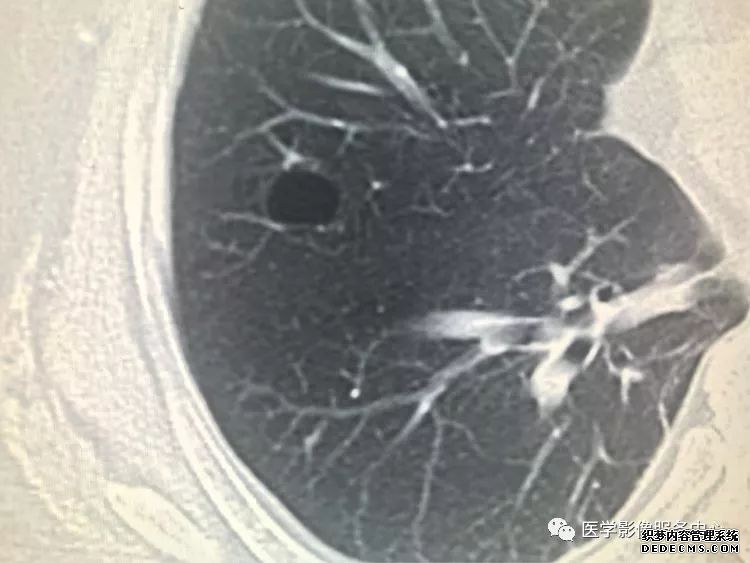

肺隔离症:易误诊为肺癌的占位性病变,肺穿刺禁忌!